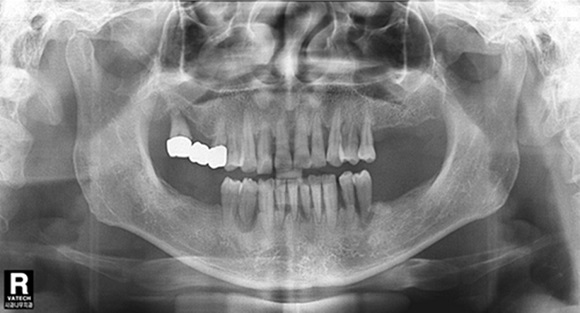

치주염을 예방하려면 치아를

깨끗하게 관리해 세균이 증식하는 것을 막는 것이 최선의 방법. 치아를 깨끗이 하기 위해서 평소 양치질을 꼼꼼히 하고, 칫솔모가 들어가지 않는

치아와 잇몸 사이, 치간은 치실이나 치간 칫솔을 사용해 꼼꼼히 닦아줘야 한다. 또한 스트레스와 면역력 관리를 위해 규칙적인 운동, 숙면, 고른